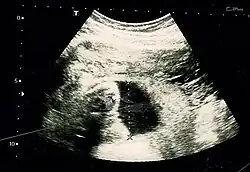

Fetus at 17 weeks

Fetal assessments

Obstetric ultrasonography is routinely used for dating the gestational age of a pregnancy from the size of the fetus, determine the number of fetuses and placentae, evaluate for an ectopic pregnancy and first trimester bleeding, the most accurate dating being in first trimester before the growth of the foetus has been significantly influenced by other factors.[22] Ultrasound is also used for detecting congenital anomalies (or other foetal anomalies) and determining the biophysical profiles (BPP), which are generally easier to detect in the second trimester when the foetal structures are larger and more developed.[23]

X-rays and computerized tomography (CT) are not used, especially in the first trimester, due to the ionizing radiation, which has teratogenic effects on the foetus.[24] No effects of magnetic resonance imaging (MRI) on the foetus have been demonstrated,[25] but this technique is too expensive for routine observation. Instead, obstetric ultrasonography is the imaging method of choice in the first trimester and throughout the pregnancy, because it emits no radiation, is portable, and allows for realtime imaging.[26]

The safety of frequent ultrasound scanning has not been confirmed. Despite this, increasing numbers of women are choosing to have additional scans for no medical purpose, such as gender scans, 3D and 4D scans.[27] A normal gestation would reveal a gestational sac, yolk sac, and fetal pole.[28]

The gestational age can be assessed by evaluating the mean gestational sac diameter (MGD) before week 6, and the crown-rump length after week 6. Multiple gestation is evaluated by the number of placentae and amniotic sacs present.[29]